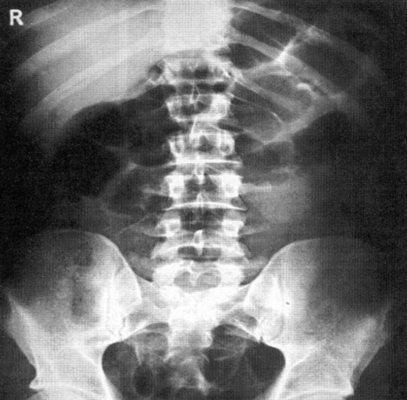

Обзорная рентгенография брюшной полости - метод бесконтрастной рентгенодиагностики состояния брюшной полости.

Для органов брюшной полости данный метод малоинформативен, так как мягкие ткани организма в большинстве своем рентгенонегативны, т.е. при таком исследовании рентгенолог не увидит изображения органов брюшной полости. По данным обзорной рентгенографии врач может только судить о наличии и распределении в брюшной полости и пищеварительном тракте газа, жидкости, а также камней или инородных тел. Метод эффективен при диагностике разрывов и перфораций полых органов брюшной полости. На снимках будет виден свободный газ в брюшной полости, которого в норме быть не должно.

Обзорная рентгенография является основным методом диагностики кишечной непроходимости (на снимках будут видны тени раздутых кишечных петель с уровнями жидкости и газа, по наличию и расположению которых можно судить о наличии и локализации непроходимости). На обзорных снимках также можно увидеть камни в почках и желчном пузыре, наличие крови и асцитической жидкости в брюшной полости.

Рентгенография органов брюшной полости

Обзорная рентгенография брюшной полости - это рентгенографическое исследование, проводящееся без введения контрастного вещества, которое позволяет получить общую картину состояния брюшной полости. Рентген позволяет обнаружить присутствие в брюшной полости свободной жидкости, инородных тел (камни в почках, камни в желчном пузыре, проглоченные предметы в кишечнике), повреждения внутренних органов и внутрибрюшное кровотечение.

Что показывает рентген брюшной полости?

Метод рентгендиагностики основан на том, что ткани различной плотности по-разному поглощают рентгеновские лучи. Более плотная, например, костная ткань хуже пропускает лучи, поэтому на снимке такая ткань оказывается светлее. Метод позволяет определить местоположение органов, их целостность, наличие инородных тел и новообразований.

Рентгенография брюшной полости показывает:

- как распределены газ и жидкость в брюшной полости, присутствует ли в брюшной полости свободная жидкость;

- присутствуют ли в брюшной полости инородные тела (проглоченные предметы в кишечнике, камни в желчном пузыре, камни в почках);

- имеются ли повреждения внутренних органов;

- имеет ли место внутрибрюшное кровотечение.

Рентген брюшной полости

С точки зрения оценки состояния конкретных органов обзорная рентгенография брюшной полости не очень информативна, однако она позволяет быстро определить, является ли картина патологической или нет. При разрыве стенки желудка или кишечника (прободение язвы или разрушении стенки опухолью) рентген покажет выходящий в свободную брюшную полость газ. С помощью рентгена брюшной полости можно диагностировать непроходимость кишечника и даже определить примерное место локализации проблемы.